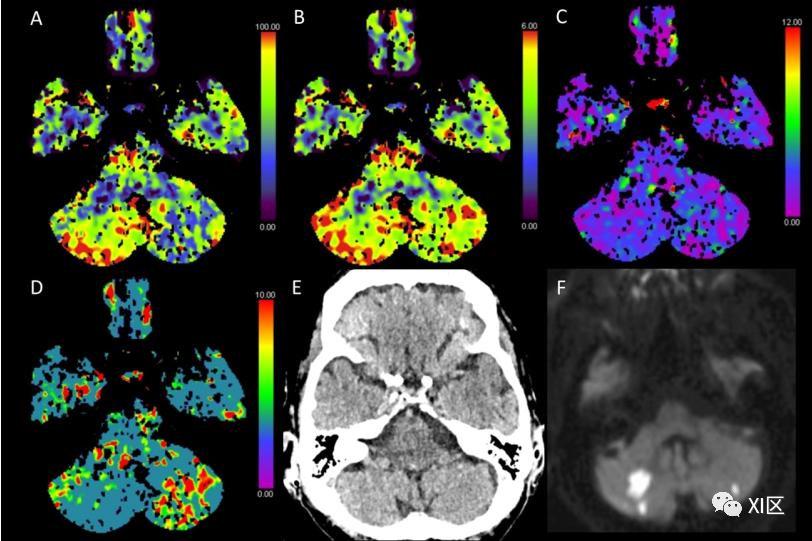

然而,由于上述CTP在技术和解剖上的局限性,特别是在小面积梗死方面,MRI被认为优于CTP。患者可在急性期出现非特异性症状,如眩晕或恶心。图6和图7给出了急性后颅窝脑梗塞的例子以及CTP检测的困难。

图6 脑部CTP产生的彩色编码图:(A)脑血流量(CBF)[mL/100 g/min],(B)脑血容量(CBV)[mL/100 g],(C)Tmax [s],以及(D)平均通过时间(MTT)[s]。(E)NECT和(F)扩散加权磁共振成像(MRI)在第二天进行。该患者在经导管主动脉瓣植入术(TAVI)后出现了手臂肌阵挛(尤其是左侧)、嗜睡和高血压。在NECT图像上,看不到明显的分界线或脑部肿胀。在CTP图上,左小脑半球的CBF降低,CBV正常,Tmax正常至轻微延长,MTT明显延长,表明后颅窝内有急性梗塞。然而,CTA上没有发现血管闭塞。与CTP的发现相反,第二天进行的MRI扫描显示左侧小脑半球有小的弥散限制,右侧有较大的弥散限制,表明双侧半球急性缺血性损伤。